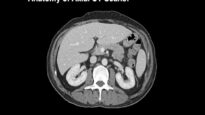

Abdominal CT scan findings

Approximately 85 percent of patients with acute pancreatitis have acute interstitial edematous pancreatitis. characterized by an enlargement of the pancreas on contrast-enhanced abdominal computed tomography (CT) scan. Approximately 15 percent of patients have necrotizing pancreatitis with necrosis of the pancreatic parenchyma, the peripancreatic tissue, or both.